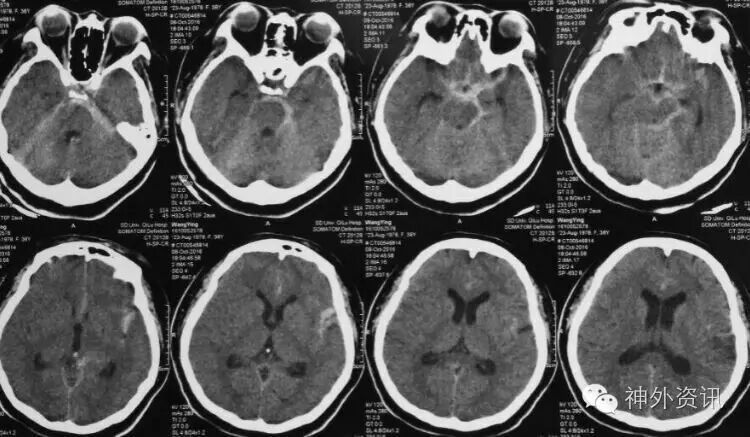

术后影像

术后cT未見术区缺血,病人语言、肢体活动正常!

术后一周3-D斜位未見BBA残留、复发,IcA管腔略有狭窄,远端血流正常!

术后一w3-D造影正位所見瘤夹及远端A1、M1及以远血管正常显影!